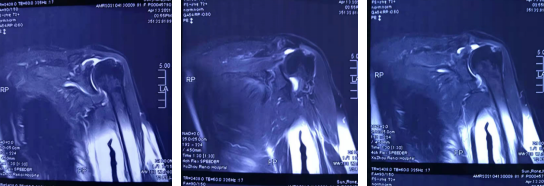

术前磁共振片

郝亮副主任医师给老人做了仔细检查,患者左肩关节僵硬,磁共振显示左肩粘连性关节囊炎,同时老人自诉还患有高血压病、冠心病,做过冠状动脉支架植入,面对如此高龄还患有诸多基础性疾病的老人,手术医生必须慎之又慎。运动医学科张传开主任和郝亮医生仔细研究患者的片子,对患者病情进行认真严谨的讨论,为使患者免于承受创伤巨大的开放手术,决定给患者开展肩关节镜探查术+滑膜清理术+肩峰下成形术。